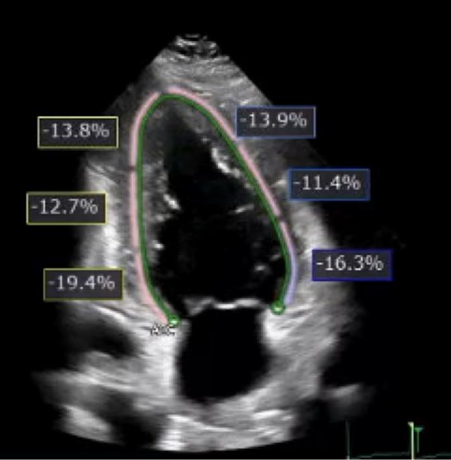

Figure 4. Transthoracic echocardiogram with evidence of reduced global longitudinal strain of -14% with reduced strain in all apical and mid-cavitary wall segments.